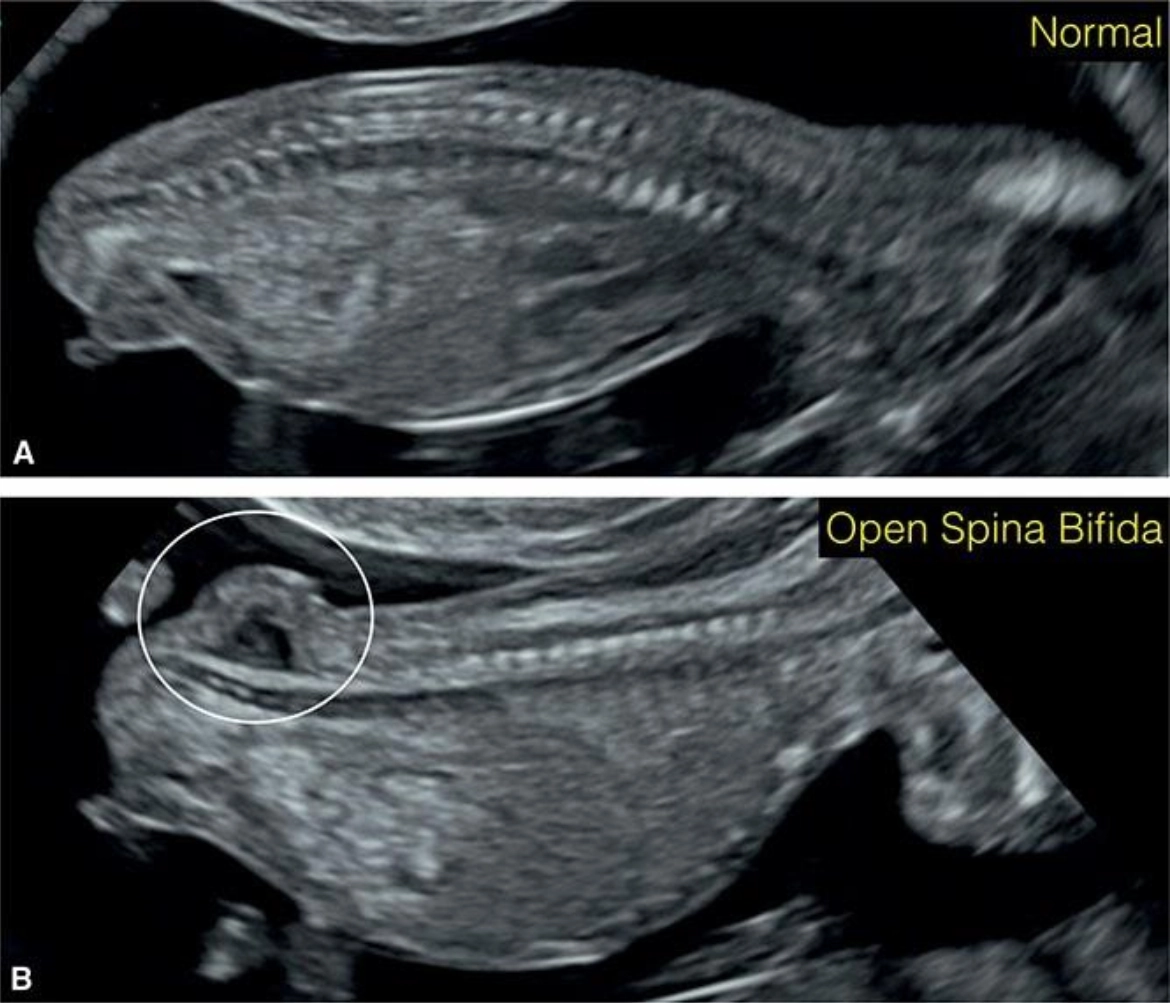

Tật chẻ đôi đốt sống thể hở (Open spina bifida)

16/03/2026